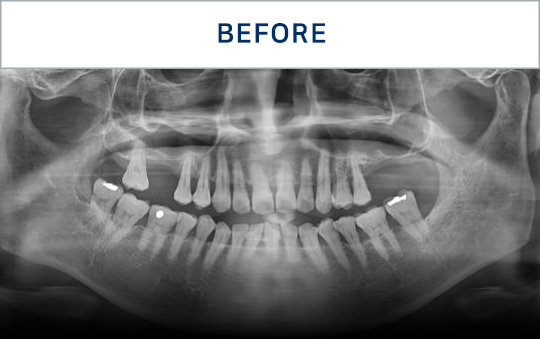

清晰可见的成果,

就是新吉种植牙

科值得信赖的证明.

通过种植牙, 让您无忧进食, 自在微笑, 重拾生活的舒适感